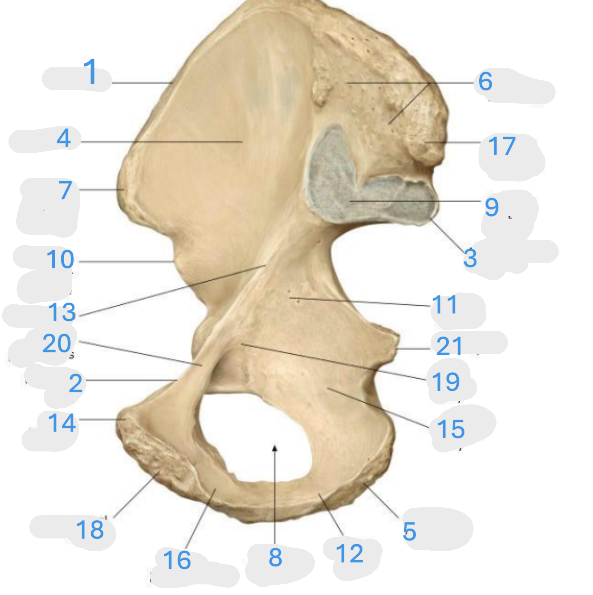

Where is the iliac crest

1

Where is the pectineal line

2

Where is the posterior iliac spine

3

Where is the iliac fossa

4

Where is the ischial tuberosity

5

Where is the iliac tuberosity

6

Where is the anterior superior iliac spine

7

Where is the obturator foramen

8

Where is the auricular surface of the ilium

9

Where is the anterior inferior iliac spine

10

Where is the ilium body

11

Where is the ischial ramus

12

Where is the arcuate line

13

Where is the pubic tubercle

14

Where is the ischium body

15

Where is the inferior pubic ramus

16

Posterior superior iliac spine

17

Where is the symphyseal surface

18

Where is the pubis body

19

Where is the superior pubic ramus

20

Where is the ischium body

21